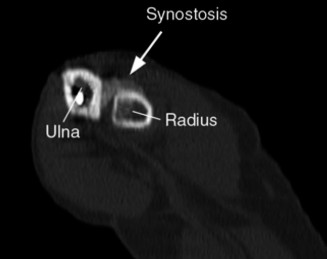

Identify the muscles that compose the force couples in the transverse and coronal planes? CASE 3 A 35-year-old male has had left shoulder pain for 4 months, ever since a low-speed motor vehicle accident (MVA). Physical examination demonstrates preserved range of motion but pain and some weakness with Jobe’s testing. His imaging is shown in Figure 2–8.

Figure 2–8_Reproduced with permission from Stadnick ME. _Partial Rotator Cuff Tears. MRI Web Clinic. 2007 (Apr).

What is the most likely diagnosis?

The correct answer is (A). These are best diagnosed on an MRI as seen in the imaging provided; addition of intra-articular contrast can further improve this study. Answer B, full-thickness rotator cuff tear, is incorrect as the bursal side of the tendon can be seen to be in continuity. Answer C, a SLAP lesion, will be visualized as a labral tear on a coronal MRI and will be found at the biceps root. Answer D, an ALPSA lesion, will be most clearly seen on an axial MRI. It is a variant of a Bankart lesion where the labrum is displaced medially and inferiorly rolling down the glenoid neck underneath the periosteum.

Rotator cuff tears are a common reason for shoulder pain and a common reason to obtain shoulder imaging. As a result, numerous different imaging modalities exist offering different pros and cons. Plain films are still the initial imaging modality of choice. These are most useful in ruling out other possible diagnosis but can help with the diagnosis of a rotator cuff tear as well. Changes to the tendon itself

may appear as calcific tendinosis, which would most commonly be seen at the bone–tendon interface. A decrease in the acromiohumeral distance (less than 2 mm) may also be indicative of a cuff tear. In late cases of rotator cuff tears, superior subluxation of the humerus may be evident. Certain variations in acromial anatomy, including spurs or a hook-shaped (type 3) acromions, may be associated with rotator cuff tears as well. With progression of rotator cuff tears, degenerative changes including spurs, cysts, and sclerosis may be evident at the greater tuberosity. In late, massive tears one may see degenerative changes consistent with rotator cuff arthropathy.

Ultrasound has been gaining popularity recently as it is extremely cost effective when compared to MRI and allows a dynamic assessment of the tendons. It has been shown to have greater than 90% specificity and sensitivity when performed by an experienced operator.

MRI remains the most popular imaging modality for diagnosing rotator cuff tears. Normal rotator cuff tendon appears dark on both T1 and T2 sequences. Tears may be noted as being full-thickness, articular-sided, bursal-sided, or intrasubstance. They are visualized as a disruption in the regular contour of the tendon and increased signal intensity on T2 sequences. Occasionally, an MR arthrogram may provide additional information regarding a cuff tear, although this is not routinely ordered.

What MRI sequence and plane is best for viewing supraspinatus rotator cuff tears?

The correct answer is (D). T2 sequence causes most soft tissues, including muscle and tendon, to appear dark and inflammation, such as at the site of a tear, to appear bright. This means that if there is a rotator cuff tear, there will be a bright spot along the course of the dark rotator cuff tendon. This is easiest to pick out in the coronal plane because the tendon runs in this plane, allowing one to view the entire supraspinatus tendon and tear in one cut.